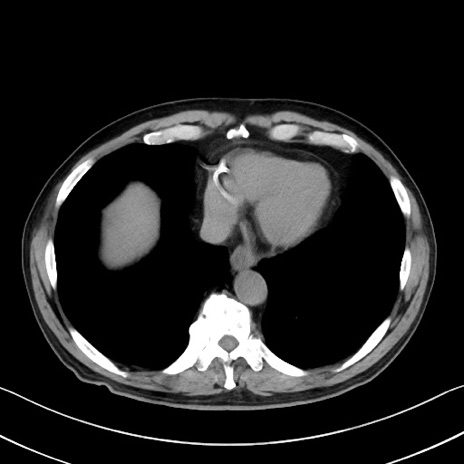

症例35(横断像)

【症例】70歳代 男性

【主訴】腹部膨満、嘔吐

【現病歴】昨日より腹部膨満感出現。本日増悪し、仙痛出現。嘔吐あり、受診。

【既往歴】糖尿病、胆摘後

【身体所見】BP 149/80mmHg、HR 74/min、BT 35.9℃、腹部:膨満、軟、圧痛なし。腸雑音減弱あり。上腹部正中切開瘢痕あり。

【データ】WBC 13500、CRP 1.72